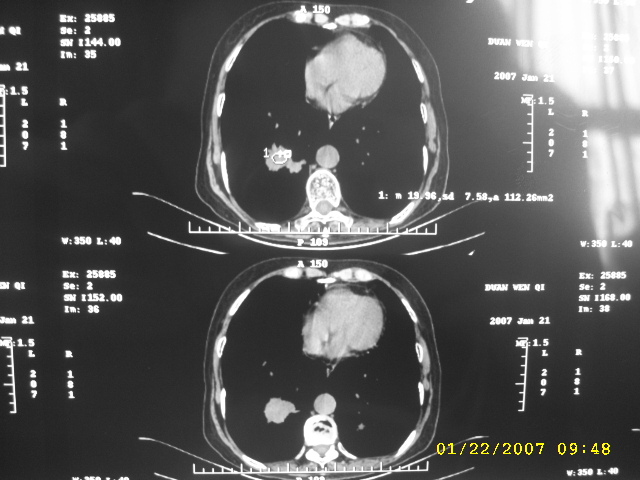

女,75.胸痛。

07.01.21.

明显的不规则形肿块,分叶、短毛刺、胸膜刺激征,血管扭曲征等周围型肺癌的征象明显,应首先考虑周围型肺癌。应与肺多发结核球相鉴别

双侧肺内块状病灶,均见分叶毛刺,左肺见典型胸膜凹陷,双侧双原发癌.